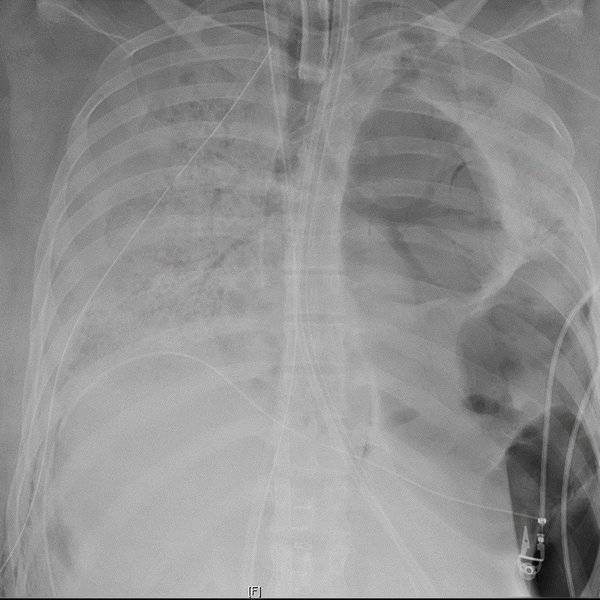

“由于COVID,她在肺部内部形成了这些空腔,这些空腔已经被感染了,这些细菌正在推动败血症的发生,”西北大学的胸外科主任Ankit Bharat博士告诉NPR。随后的图片显示了患者的胸部X光片,它揭示了那些异常空腔的存在(较暗的区域),以及患者的一个受损肺部。